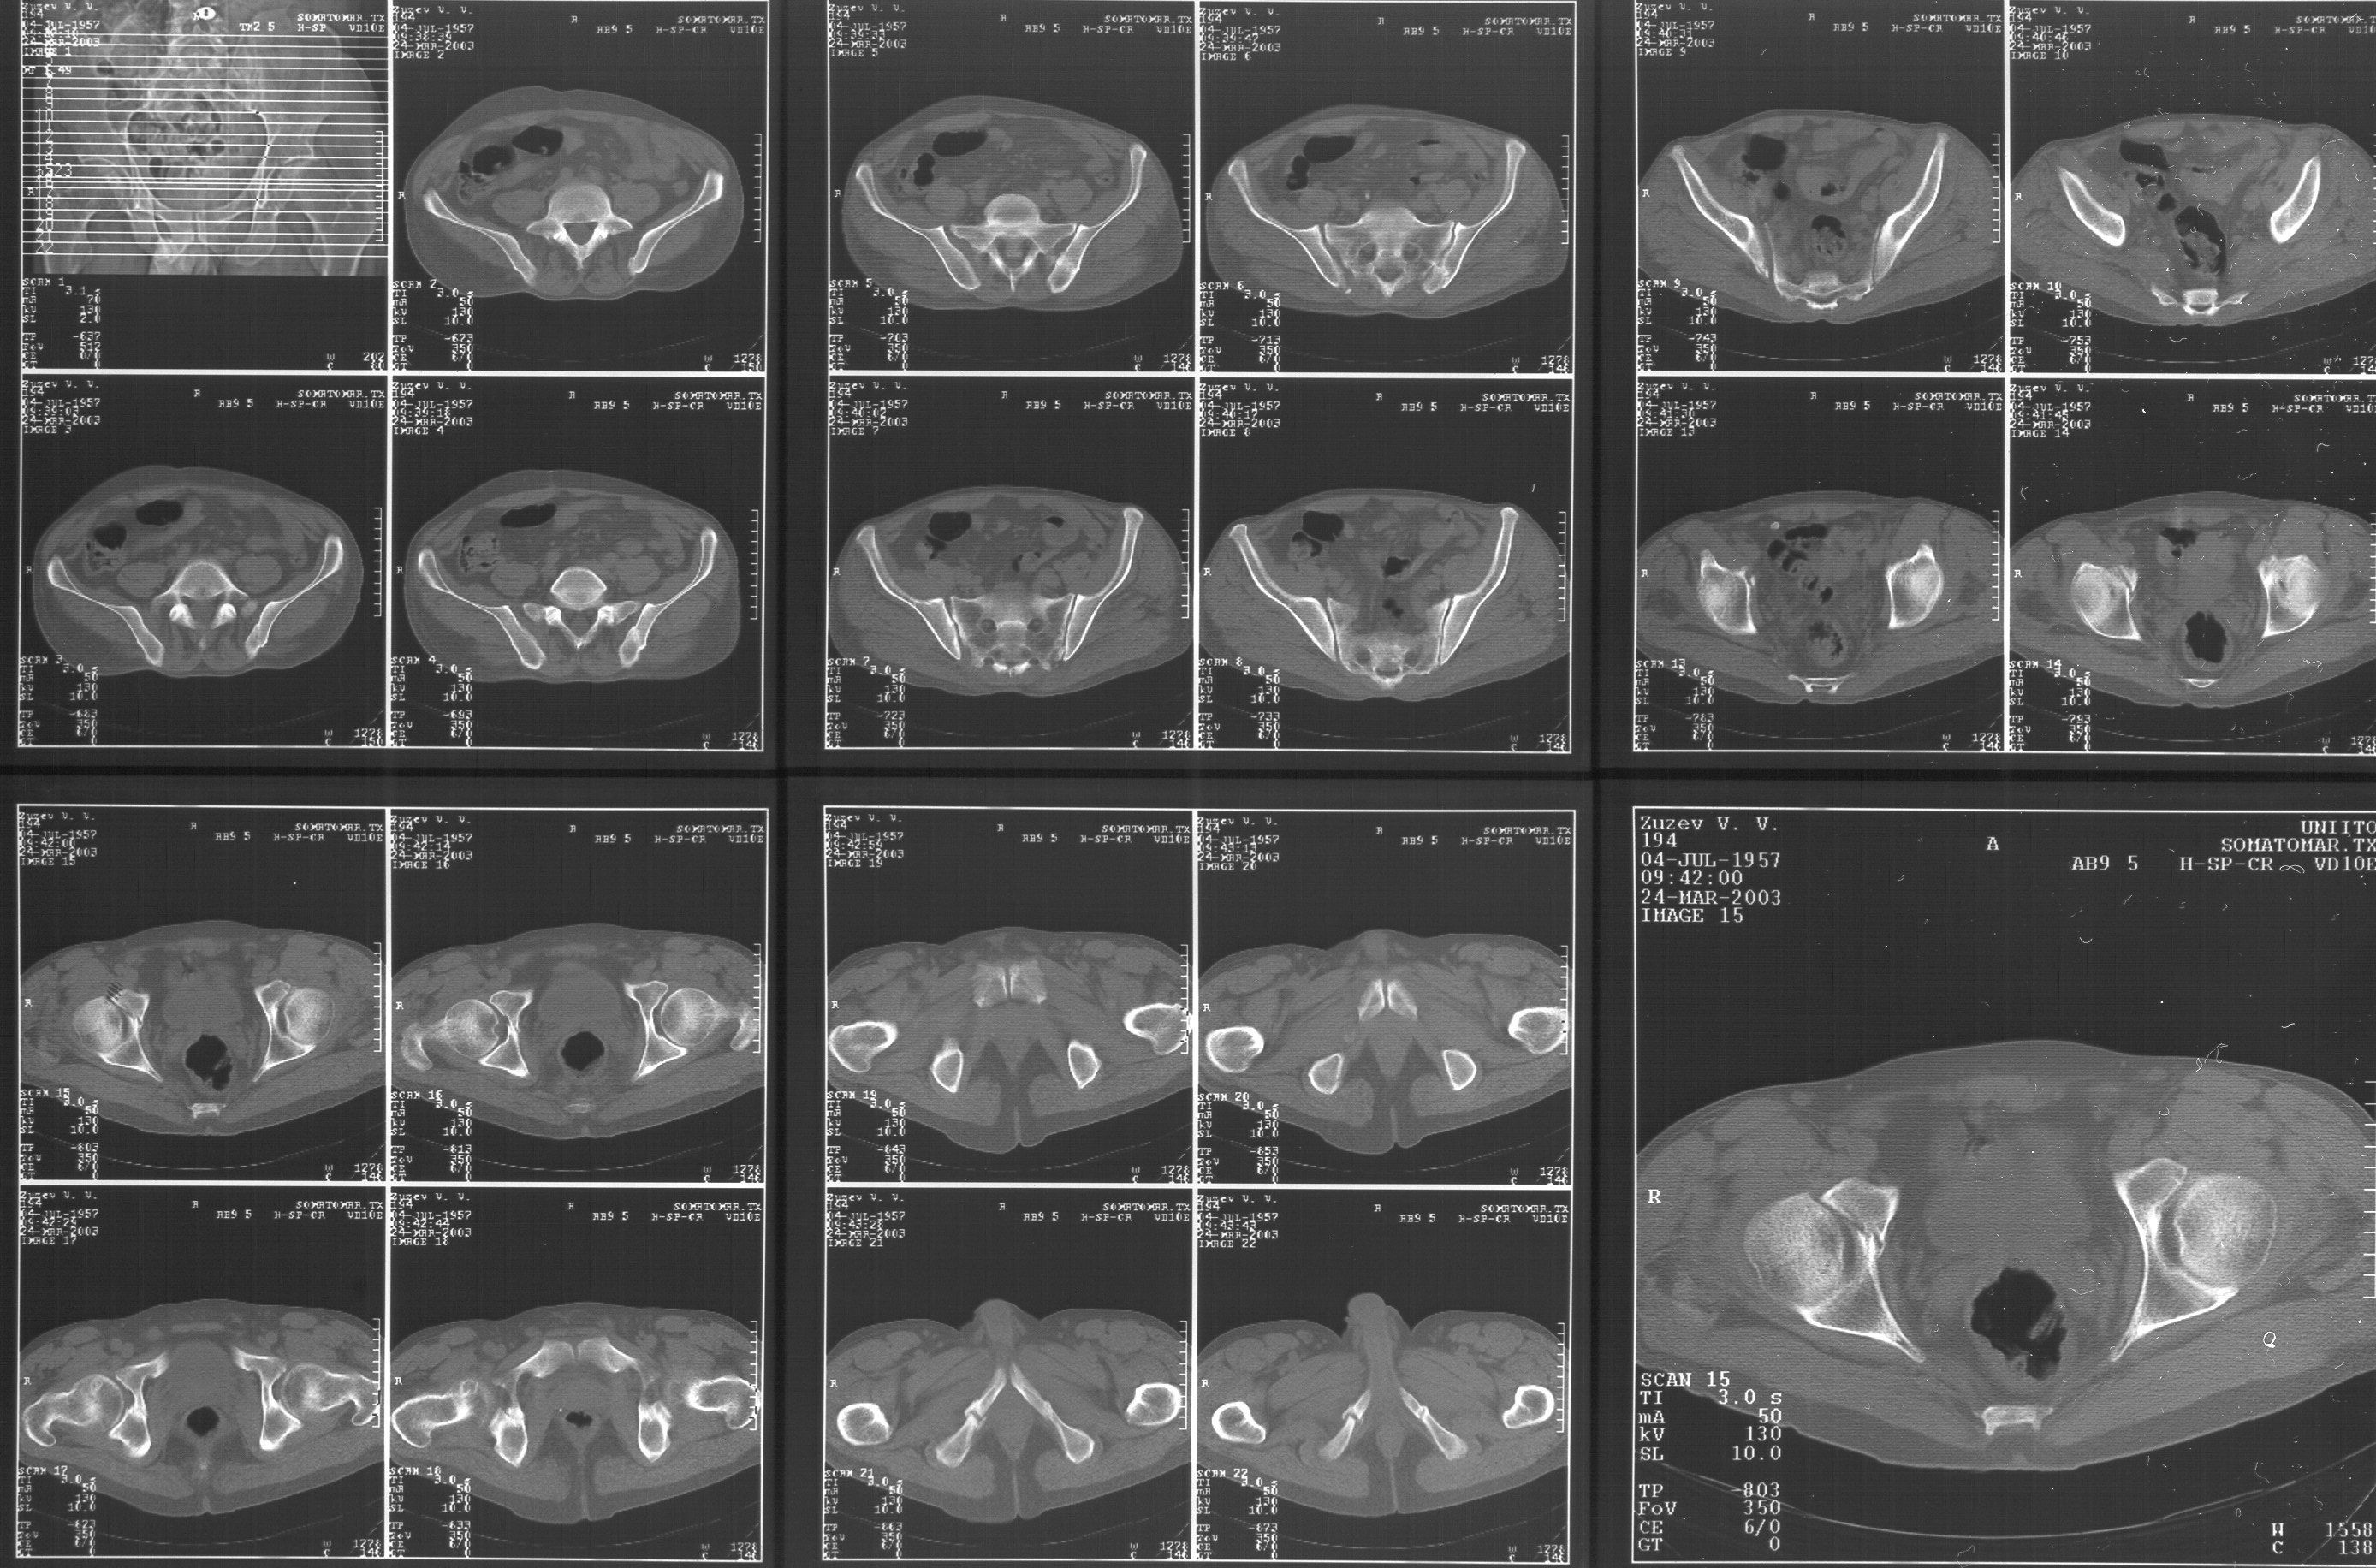

Прилагаю свежую КТ таза.

Буду признателен за комментарии и предложения по тактике.

Картинки см. ниже, левая - с экранным разрешением, вторая - полноразмерная, ~900 кб.

Based on the CT images you provided, he appears to have a nonunion of the the right ischium, which would explain his symptoms. General principles of treatment of hypertrophic (which this appears to be) nonunions suggest rigid fixation, but I'm not sure what the best approach would be. Could get a lag screw across the fracture through a Kocher-Langenbeck approach or plate osteosynthesis through direct ischial approach, but perhaps Chip, Adam or someone with more pelvic fracture experience could enlighten us all.

I think the CT cuts in question are on the right of the bottom row i.e.

http://www.hwbf.org/hwb/conf/alex47/image3a.jpg

I think this is just a pelvic ring disruption that has gone on to a non-union. The arrow is pointing to the inferior ramus non-union, and

the sup ramus is a high "root" fracture, right near the pecten. The sup ramus fracture enters the tab - you could call it an acetabular

fracture - but down here in Dallas we treat these acutely as stable pelvic ring injuries. The fracture in the anterior portion of the

acetabulum is so low it doesn't seem to cause much trouble.

His R sacroiliac joint is opened anteriorly a little bit - the "unreduced posterior lesion" Alex mentioned in his first post. My earlier post about plating, bone grafting, etc., is all wrong.

What you have is a pelvic fracture that hasn't healed after 4 months or so, with a minimal deformity.

I think what I would offer the guy is a percutaneous iliosacral screw to stabilize and improve the SI joint alignment, coupled with a perc anterior column screw to stabilize the high ramus fx. These screws aren't easy to place, and have a host of potential problems and complications. But, I think they would work.

Виноват, первый раз не обратил внимания на возможность полноформатного просмотра томограмм. В этой связи -дополнения к своему первому комментарию: сросшийся перелом вертлужной впадины справа, L5-S1 спондилоартроз, расширение суставной щели крестцово-подвдзошного сочленения справа может компрометировать его стабильность и вызывать локальные боли, но вряд ли это может давать двусторонние проявления в нижних конечностях. Все-таки миелограмма или ЯМР желательно иметь, чтобы определиться в тактике.

Речь идёт о коплексном двустороннем повреждении таза с нарушением тазового кольца.

А именно: разрыв илио-сакрального сочленения справа, на этой же стороне трансацетабулярный перелом с незначительным смещением, перелом подвздошной кости слева. Исходя из вышеперечисленного, меня не удивляют двусторонние жалобы пациента. Однако, учитывая представленные снимки ЯМР и времени, прошедшим с момента травмы мне представляется пока преждевременным говорить об образовании ложных суставов. Судя по развиввшейся костной мозоли в области вышеперечисленных очагов, все переломы находяться в стадии консолидации. Вполне возможно, однако, что трансацетабулярный перелом приведёт в дальнейшем к развитию посттравматического артроза ТБ- сустава.

Поэтому тактику лечения я бы выбрал консервативную. Через 6 Месяцев ЯМР можно повторить. Не думаю, что транскутанная фиксация винтами приведёт к облегчению болей пациента. При подобной ситуации (см. выше) боли могут сохраняться до года.